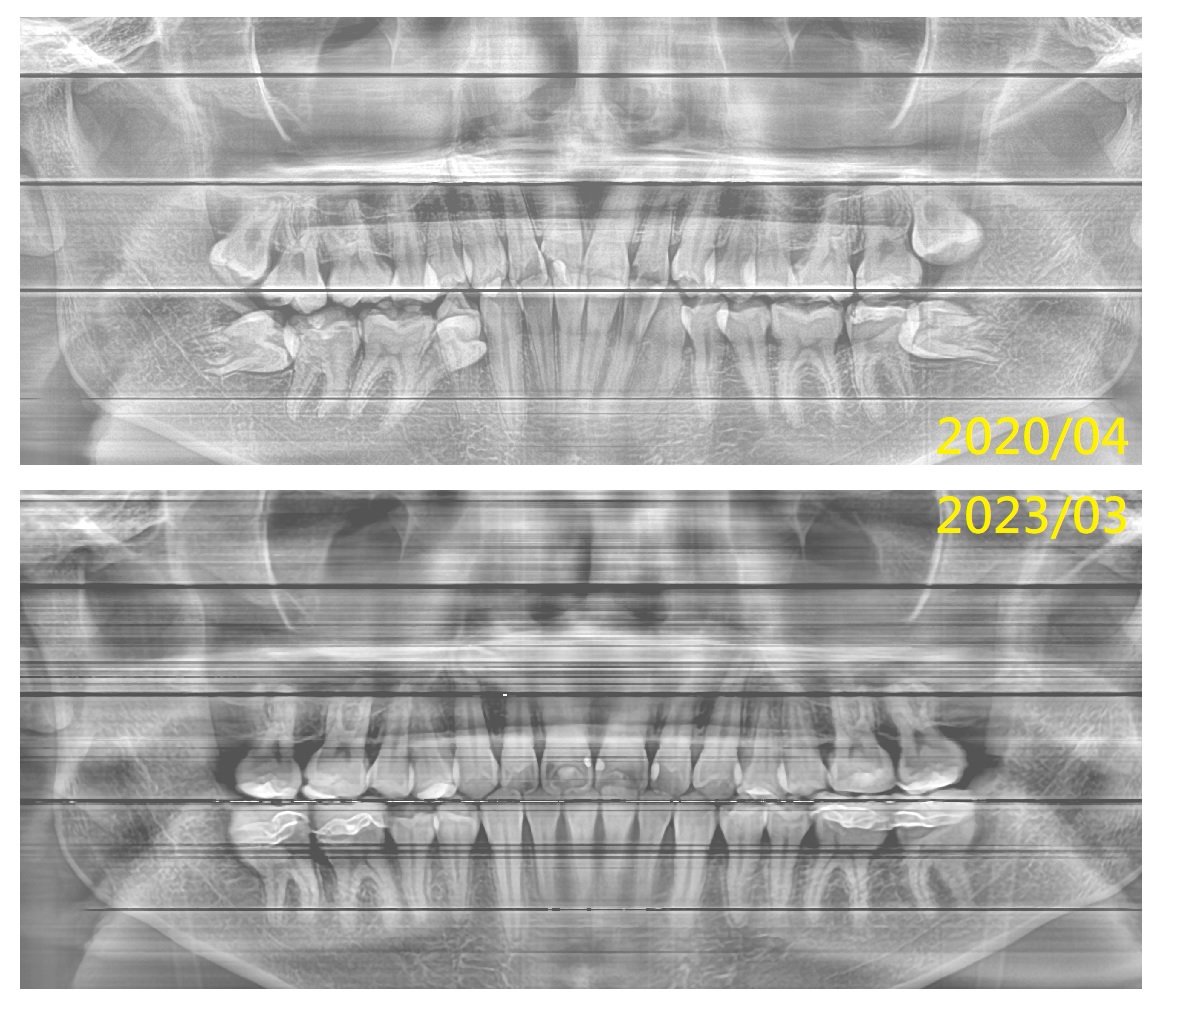

患者年約二十初頭歲,因牙齒重疊非常嚴重,但却不知自己牙齒問題,於門診中表示要補蛀牙,經醫師檢查後,醫師告知需做咬合調整和矯正治療,方可解決牙齒塞東西,不斷蛀在特定位置的困擾,患者聽後,非常高興有方法可以解決,於是印模做仔細評估。

經醫師詳細分析,家長也到場確認不需拔除任何一顆小臼齒後,但需將4顆埋伏智齒拔除,決定進入療程,希望可以改善牙齒的問題也讓咀嚼功能恢復。

上顎已被推擠成牙齒往外飇出。

牙齒刷得不錯,但因排列極差,所以咀嚼功能不佳,但牙縫易塞食物。牙縫有蛀牙現象。

歷經快三年的調整,牙齒終於達到患者的理想標準,大幅改善了牙齒外觀、牙弓形態及整體功能。

除牙縫嵌塞問題不再困擾著他,功能改善也提高了患者的飲食意願。

除以前造成的牙縫蛀牙略有色差以外,其餘大致完美。開心的結束療程。